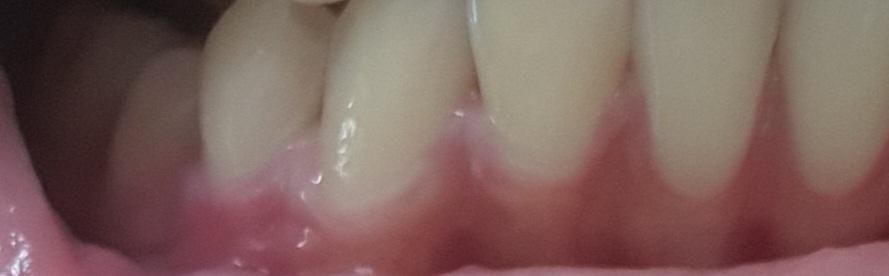

치아와 가까운 잇몸이 하얀색인데 괜찮나요?

잇몸이랑 치아가 닿은 부분이 점점 하얀색?으로 좀 변해가는 거 같은데 이거 원래 이런가요?

전에는 이정도로 넓지 않아서요..

잇몸이 얇은 부위는 하얗게 보일 수 있습니다. 교정중에 잇몸이 약해질 수 있어 관리잘해주셔야 합니다.

치아와 닿고 있는 부분의 잇몸은 얇기 때문에 하얀색으로 보이는 것이 정상입니다. 문제가 있는 것은 아니기 때문에 걱정하지 않으셔도 될 것으로 생각됩니다.

잇몸에 부분적으로 염증이 있으면 잇몸 색상 변화가 있을 수 있습니다. 치과가서 잇몸체크해보고 필요하다면 잇몸치료, 스케일링 받으시기 바랍니다.